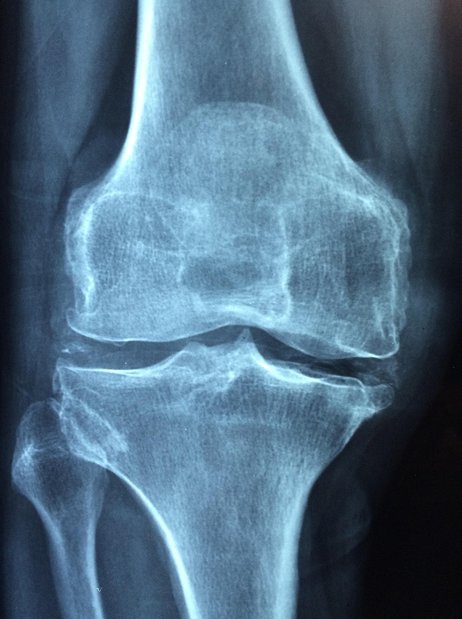

골다공증은 뼈의 강도가 약해져 작은 충격에도 쉽게 부러지는 상태를 의미합니다.

뼈는 끊임없이 오래된 조직을 제거하고 새로운 조직으로 대체하는 재형성 과정을 거치는데, 이 균형이 깨지면서 뼈의 밀도가 감소하고 미세 구조가 손상됩니다.

결과적으로 척추 압박 골절, 고관절 골절, 손목 골절 등 심각한 골절이 발생하여 통증, 자세 변형, 활동 제한을 초래하고 심지어는 사망률 증가에도 영향을 미칠 수 있습니다.